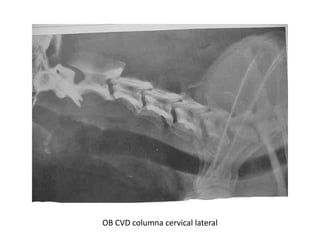

OB CVD columna cervical lateral